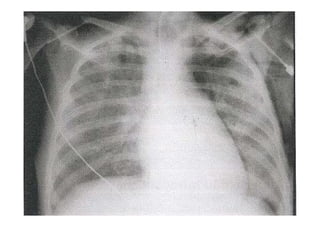

Radiografia e TC de tórax

Utiliza-se com frequênciap/ avaliar: O posicionamento do TOT: 4-6 cm acima da carina; Se os pulmões estão sendo aerados adequadamente; Alterações patológicas e diagnóstico de pneumopatias; Outros. Radiografia e TC de tórax